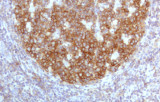

- Linfoma follicolare: tipici pattern di co-espressione (es. CD10 con BCL2 aberrante).

- LLC/LLS: co-espressione caratteristica di CD5 e CD23 nelle cellule B CD20+ (l'interpretazione richiede consapevolezza del pattern perché sono presenti cellule T reattive).